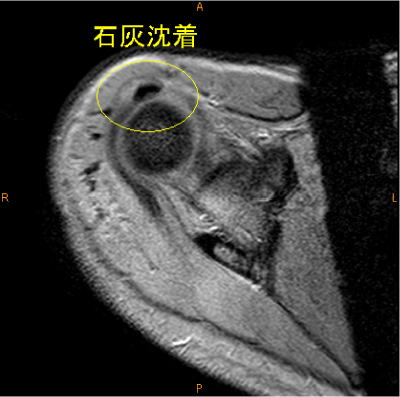

MRI所見

陳旧性石灰沈着性腱板炎のために肩峰下の擦れを生じていると考えられる症例。

石灰沈着は脂肪抑制T2, T2*

画像で気がつきやすい。

診断

陳旧性石灰沈着性腱板炎、擦れ、断裂(-)